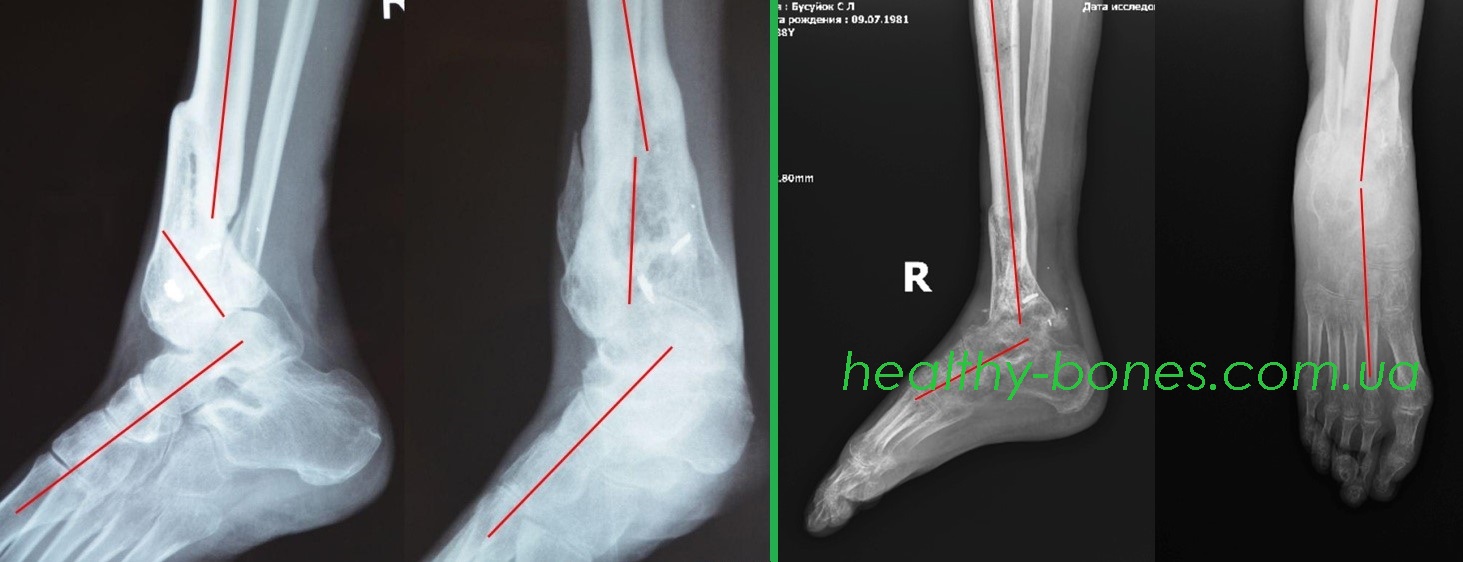

В результате боевых действий в зоне проведения АТО получил осколочное ранение голени с многооскольчатым переломом дистальной трети правой большеберцовой кости и надлодыжечным перелом малоберцовой кости. Лечился в военном госпитале. Переломы срослись с укорочением и сложными угловыми и ротационной деформацией.

По рекомендации волонтеров обратился к нам за помощью. Нами были проведены этапные операции, направленные на устранение всех видов деформации и укорочения конечности. Через 2 года после начала лечения Сергей смог полноценно пользоваться своей правой ногой.